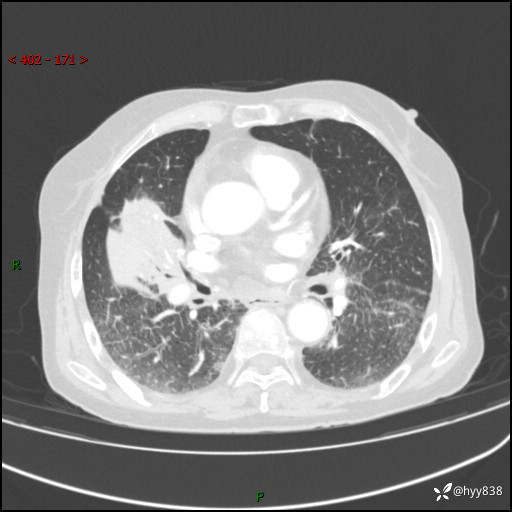

胸部CT增强(外院平扫)